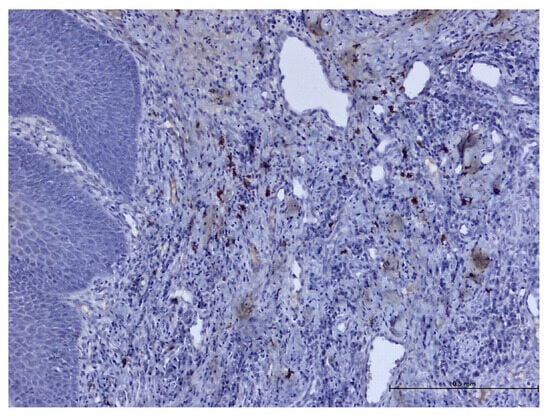

3. Results